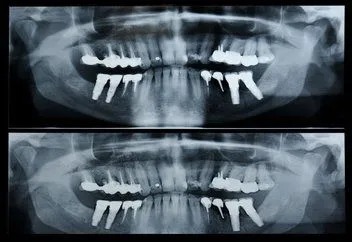

Panorex

A panoramic x-ray  is capable of identifying many issues and structures that a normal x-ray is unable to identify. Initially you may sit in a chair with your chin on a small ledge. Once positioned in the machine, it will rotate around your entire head taking a full 360 degree view of the teeth, head, sinuses and bones.

The ability to view the full structure of your head as a whole is very informative to the dentist. It will allow us to see any potential problems and make sure that everything is functioning as it should be. The x-ray is capable of viewing specific types of structural problems, infections, wisdom teeth or asymmetry among others potential issues.